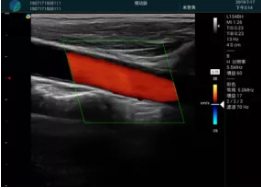

可視化甲狀腺穿刺引導(dǎo)

頸動脈血流充盈飽滿,無外溢

肝內(nèi)血管顯示清晰,血流敏感無外溢

2001年美國健康護(hù)理研究和質(zhì)量監(jiān)督局(AHRQ)批準(zhǔn)了一項(xiàng)關(guān)于提高患者安全性的報(bào)告,建議:在頸內(nèi)靜脈中心置管術(shù)時使用超聲引導(dǎo)。此后超聲引導(dǎo)穿刺被用于幾乎所有的急診穿刺操作,尤其是血管穿刺。

便攜超聲在急診穿刺中的應(yīng)用:

* 提高了穿刺成功率

* 減少了穿刺損傷及并發(fā)癥

* 縮短了操作時間

* 減輕了患者痛苦